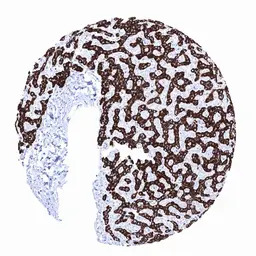

IHC-P analysis of human liver tissue section using GTX04478 Hepatocyte Specific Antigen antibody [MSVA-OCE5] HistoMAX.

Strong Hepatocyte staining in hepatocytes while other structures of the liver remain negative.